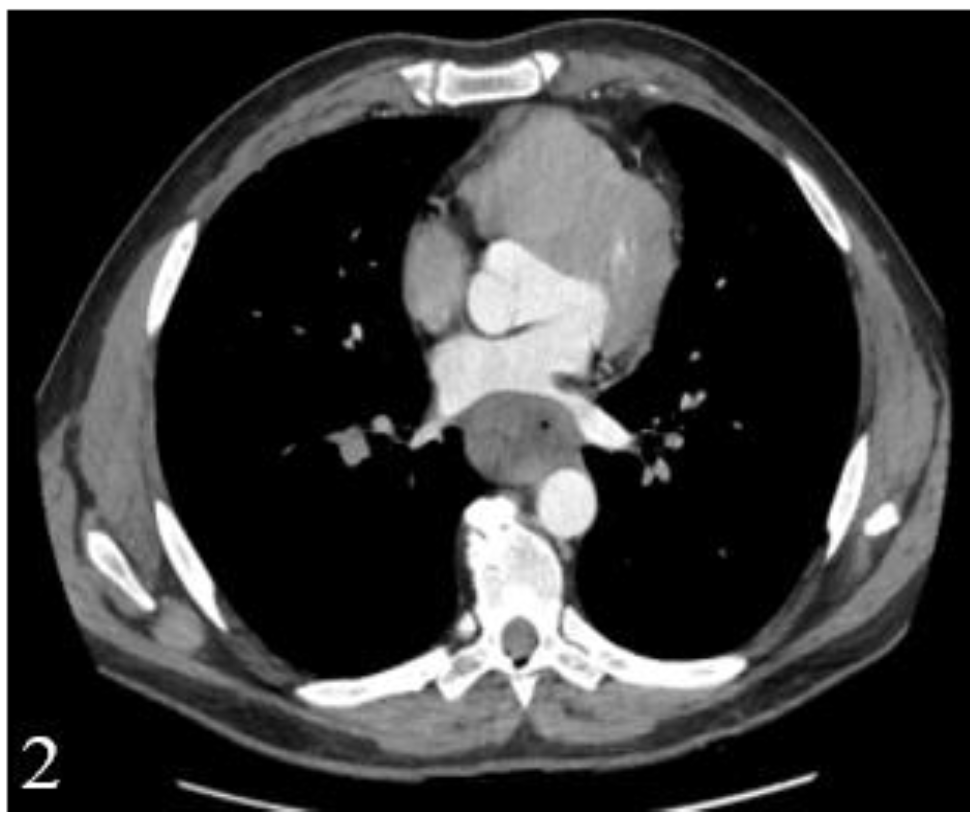

Figure 4.

EUS image showing a round lymph node with preserved hilum, with a diameter under 10 mm, located in the hepatic hilum.